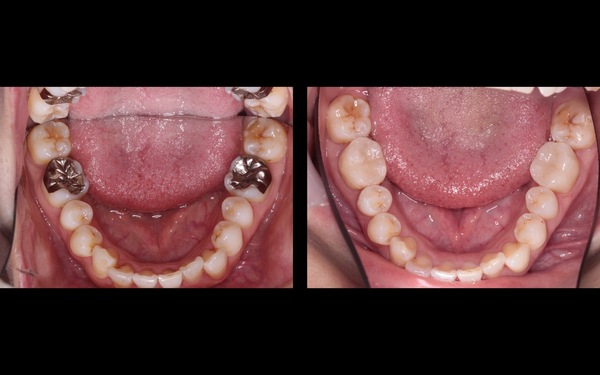

治療写真 術前 パラジウムインレー(銀歯)。10年以上が経過し劣化している。 術後 適合精度の高い(ぴったりと合った)クラウンおよびインレーが装着された。色調も調和している。 パラジウムクラウンを除去し仮歯に置き換えた。5,9 Posts See Instagram photos and videos from '銀歯' hashtag30代女性 銀歯をダイレクトボンディングで白く治療した症例 ご相談内容 笑ったときに銀歯が見えるのが気になっていたそうです。 歯を白くしたい、永く保つようにしたいとのことでご相談くださいました。 診断結果 ご相談のとおり、下の奥歯が銀歯で